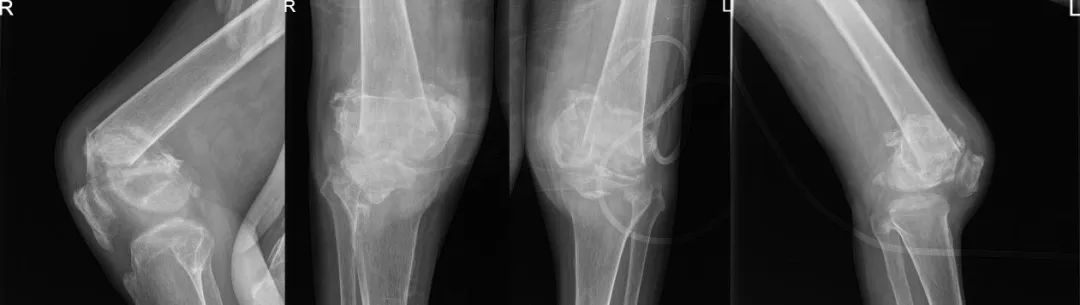

术前X线:双侧膝关节结构紊乱

63岁的辜先生是一位沪上“985”大学的教授,15年前一场突如其来的车祸引起颈椎外伤并导致部分瘫痪,从此无法正常行走,但双下肢尚能站立给了他最后的安慰,让他不至于绝望。但3个月前,噩运再次降临:在进行康复运动的时候,辜先生不幸摔倒,双侧膝关节明显畸形,当地医院诊断为双侧股骨远端严重粉碎性骨折。由于长时间卧床所致严重的骨质疏松及长久肺炎所致的呼吸衰竭,让骨科和麻醉科医师都望而却步。带着畸形的双侧膝关节,他辗转沪上多家大医院未果。失望之际,他带了一丝期许,慕名来到同济大学附属同济医院,骨科副主任、骨科创伤骨科主任樊健教授为其分析病情后,决心勇挑重担,帮助辜先生实现站立的愿望。